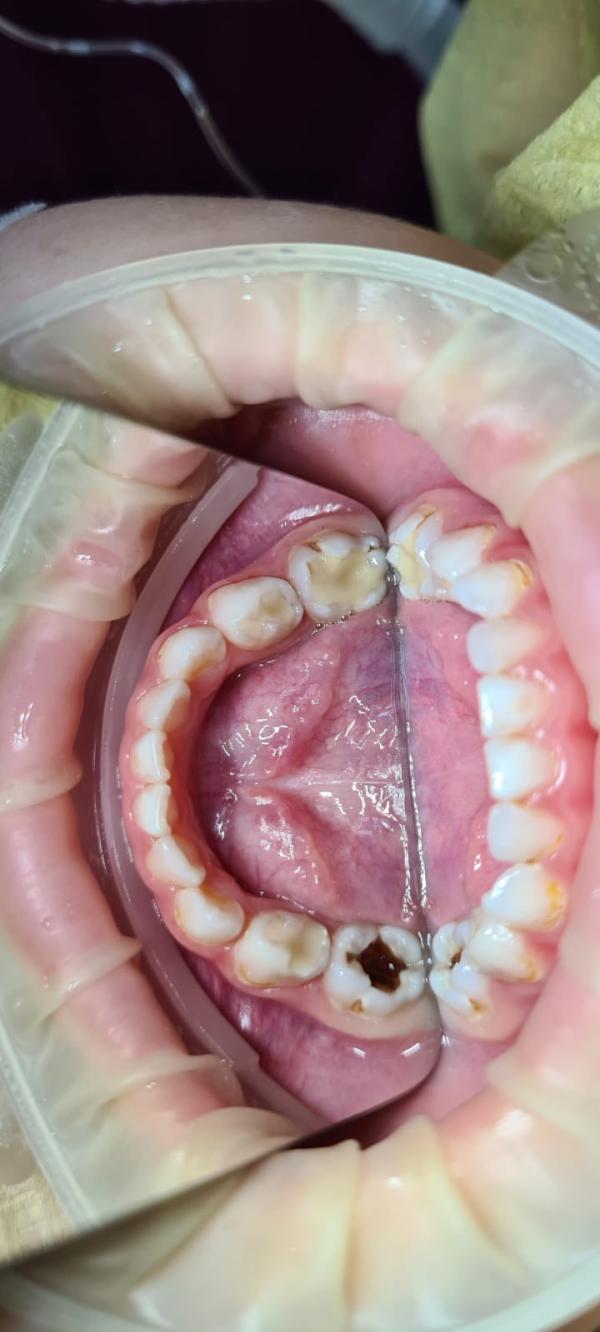

Наш врач Филиппов Григорий, астынныбыт аган от проделанной работы. Все вышло на 128тысяч, рассчитывали на 118. Ынырык астыктыктык онордо все зубы😍

Под наркозом 4 часа 15 минут, после наркоза проснулась через 30 минут. Не плакали, не капризничали хата, домой пришли сидим кушаем🥰

Вуаааа,9 тииспитин кариес булбуттара бугун☹️аюая..Отостом чо то отзыв плохие ди сорохторго туьэн хаалар диэн ,ТТТ боюсь